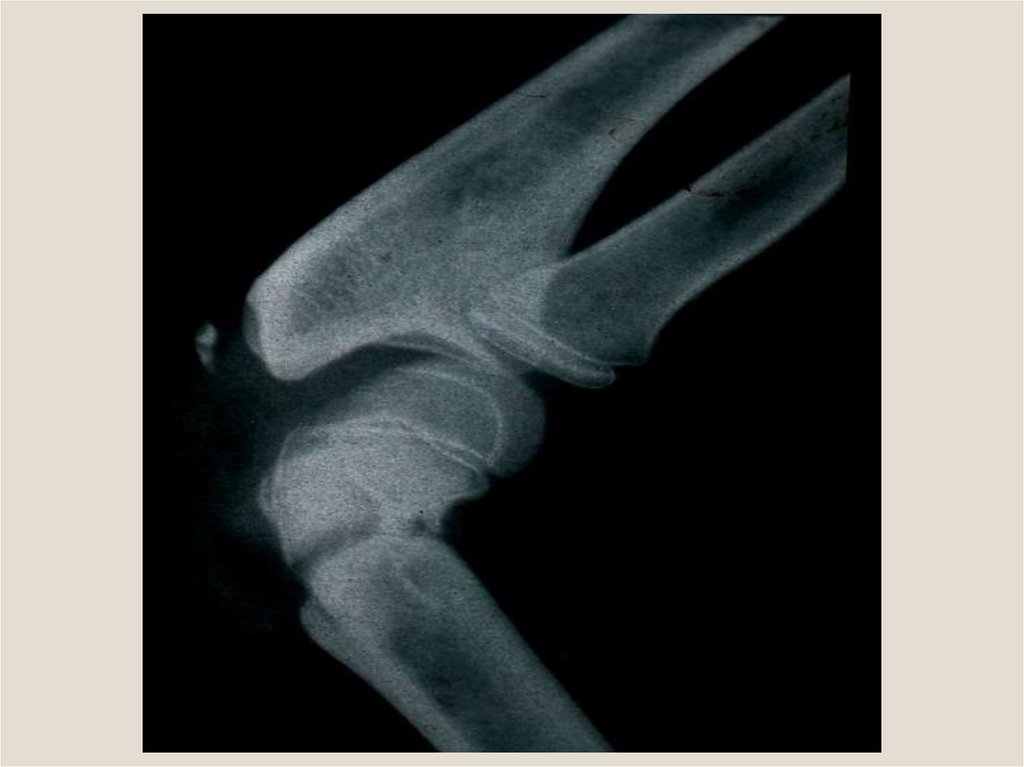

Репозиционная: до 3 дней. Желательно продолжительность

этой фазы сократить до минимума. Поэтому контрольная

рентгенограмма после наложения скелетного вытяжения должна

быть сделана уже на следующий день. После этого следует

произвести коррекцию величины силы натяжения, ее

направления, наложить дополнительные тяги. Чем дольше

продолжается фаза репозиции, тем хуже условия для образования

первичной мозоли. Репозиция отломков должна быть

подтверждена рентгенограммами в двух проекциях.

Ретенционная (удержание): 2—3 нед. В этот период должен

быть обеспечен максимальный покой вытягиваемого сегмента

конечности (вред от перекладываний больного, транспортировки

его, включение в лечебную физкультуру поврежденного

сегмента). Через 2 нед после начала вытяжения следует сделать

ТРИ

ФАЗЫ ЛЕЧЕНИЯ ПЕРЕЛОМОВ СКЕЛЕТНЫМ

контрольные рентгеновские снимки в двух проекциях.

ВЫТЯЖЕНИЕМ

Репарационная: 2—4 нед — от первых признаков мозоли до

достаточной консолидации (прекращение вытяжения).

Клинически это подтверждается тем, что больной может поднять

поврежденную конечность.